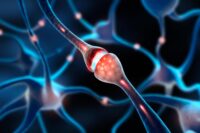

Summary of Scientists Discover Ultrasound May Stop Arthritis Before It Starts: Researchers at The University of Alabama in Huntsville have found that continuous low-intensity ultrasound may help reprogram immune cells…